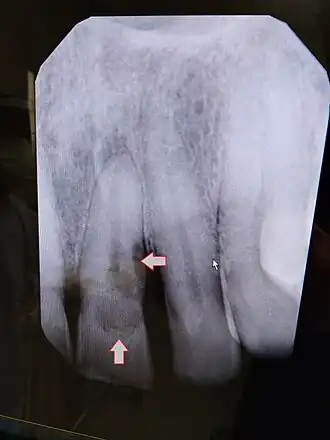

External Inflammatory Root Resorption

External inflammatory root resorption may be caused by trauma to the root surface, due to damage to the periodontal ligament (PDL) and/or extended drying following tooth avulsion. Following trauma, dentinal tubules are exposed leading to communication with an infective or necrotic pulp. This leads to an inflammatory process that causes external root resorption.[16]